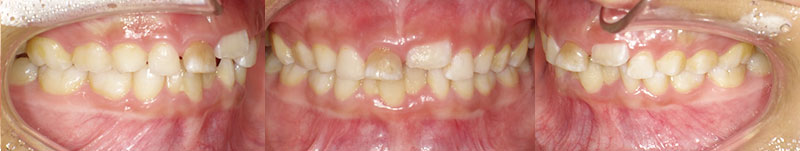

| 初診時口腔内写真 |

|---|

![]() |